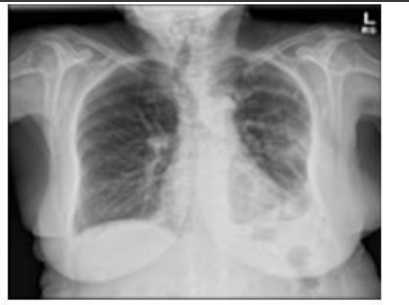

A 74-year.old woman with a past medical history significant for essential hypertension, former smoker, and goiter presented to the urgency room with dyspnea on exertion of one month of evolution, 'Ihe patient has no known asbestos exposure. Physical examination was remarkable for decreased breath sounds on the left hemithorax, Chest Xray was initially evaluated and showed evidence of near complete opacification of the left lung, Given this finding, a chest CT scan was performed which revealed a 15.1 cm x II cm x 19.3 cm extrapulmonary and intrapulmonary mass in the left hemithorax with compression and subtotal collapse of the left lower lung, A PET CT scan was also performed and showed a 13 cm FDG avid mass in the left chest involving nearly all the left lower lung, and the posterior segment of the left upper lung. This is a tool which helps to categorizæ the tumor between malignant and benign, depending on the of its metabolic activity